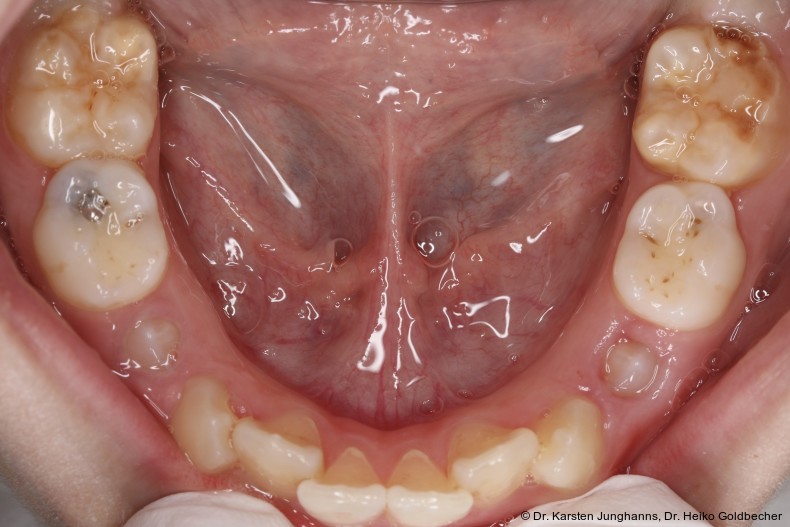

Eine Patientin stellte sich im Alter von neun Jahren erstmals vor. An den ersten Molaren des Unterkiefers wurden vom Hauzahnarzt eine MIH diagnostiziert (Abb. 1a) und die Zähne als nicht erhaltungsfähig eingestuft. Die beiden ersten Molaren wurden hemiseziert und der distale Anteil extrahiert. Gut zu erkennen ist auf dem OPG die annähernd achsengerechte Mesialisierung der zweiten Molaren sowie die Aufwanderung der Zahnkeime der dritten Molaren (Abb 1b: ca. 1,5 Jahre nach Hemisektion). Noch vor Durchbruch der zweiten Molaren in die Mundhöhle wurde auch der mesiale Anteil entfernt. Der spontane Lückenschluss erfolgte innerhalb der nächsten anderthalb Jahre (Abb. 1c). Die endgültige Achsstellung kann nach Ausdehnung der Teilmultibandapparatur eingestellt werden.